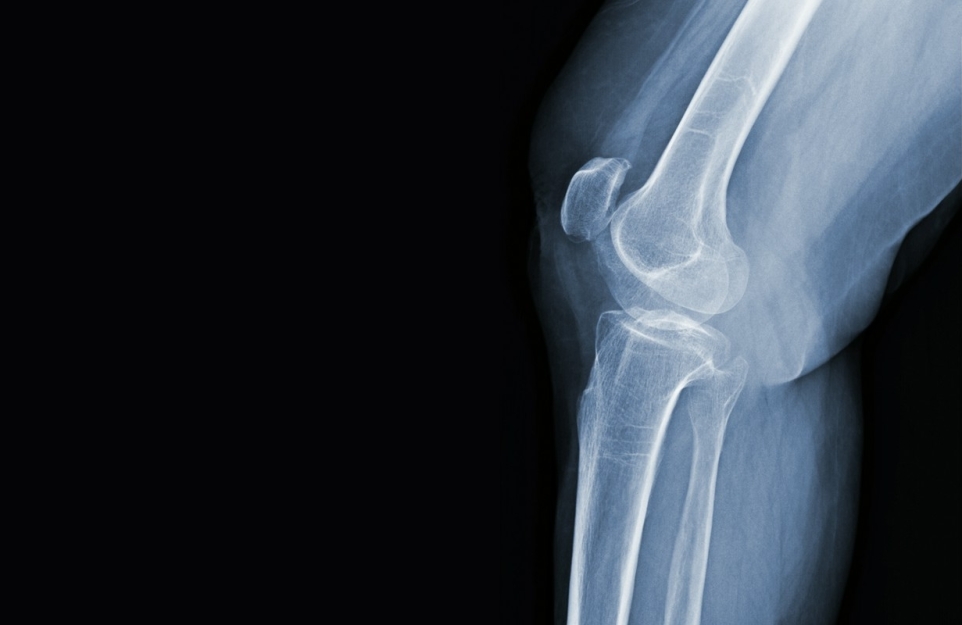

Skrzypiące kolana to częste zjawisko, które może budzić niepokój, zwłaszcza gdy pojawia się jednocześnie z dolegliwościami bólowymi. Choć nierzadko jest to objaw niegroźny, bywa też sygnałem poważniejszych zaburzeń związanych ze zdrowiem stawów.

Innym źródłem takich dźwięków bywają zaburzenia ustawienia rzepki lub zmiany zwyrodnieniowe chrząstki. Tarcie elementów stawowych, w tym ścięgien oraz powięzi, również może prowadzić do odczuwalnego trzeszczenia. Choć samo skrzypienie u osób ogólnie zdrowych często nie wiąże się z bólem, powinno zwrócić uwagę, jeśli pojawia się równocześnie ból kolan, uczucie sztywności albo inne niepokojące symptomy.

Gdy skrzypieniu w stawach kolanowych towarzyszy ból, obrzęk, uczucie blokowania ruchu lub wyraźne ograniczenie zakresu zginania i prostowania, warto skonsultować się z lekarzem. Podłożem takich dolegliwości mogą być urazy mechaniczne, przewlekłe przeciążenia, nadmierna masa ciała, a także schorzenia o podłożu zapalnym, na przykład reumatoidalne zapalenie stawów.

Do istotnych czynników ryzyka zalicza się wiek powyżej 65. roku życia, nieprawidłowości w budowie i ustawieniu kończyn, takie jak koślawość kolan czy skrzywienia kręgosłupa, a także uwarunkowania rodzinne. Wczesne rozpoznanie nieprawidłowości ma duże znaczenie dla zapobiegania dalszym powikłaniom, w tym choroby kolan o charakterze zwyrodnieniowym oraz stopniowego uszkadzania struktur stawowych.